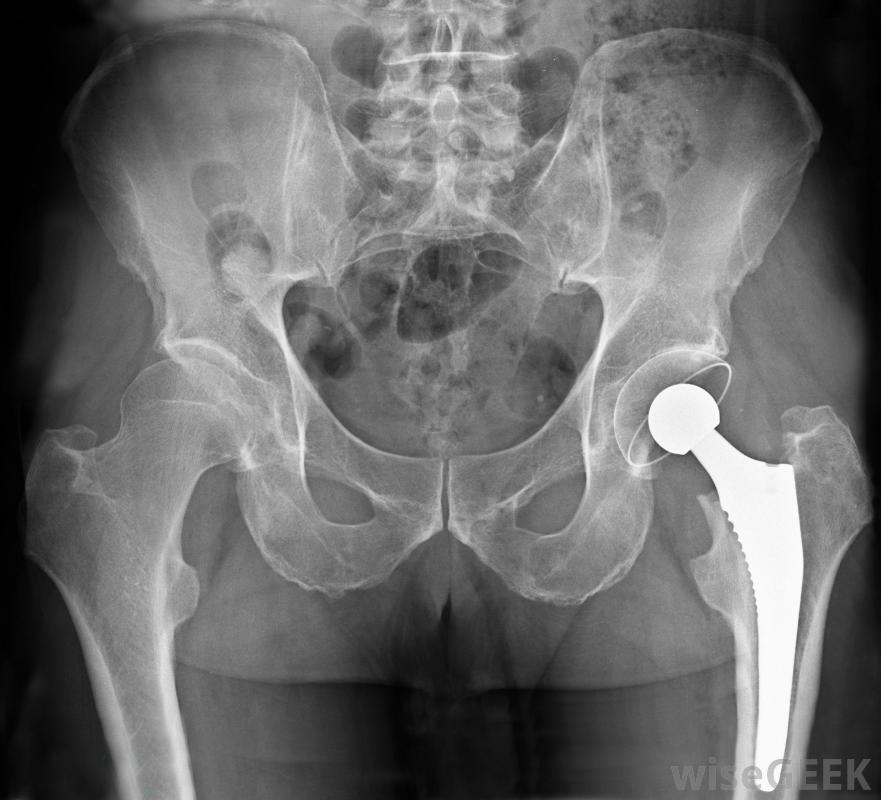

髖關節置換手術有時是選擇性手術。